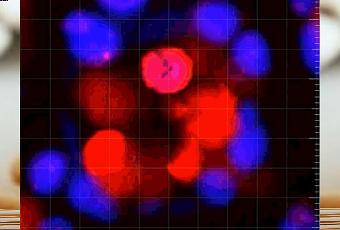

Les chercheurs de l’Académie Sahlgrenska, Université de Göteborg décrypten comment ces cellules sentinelles et suicidaires gèrent et coordonnent la protection des sites les plus sensibles du côlon, en détectant les bactéries qui viennent de pénétrer la barrière de mucus protecteur puis en déclenchant une » cascade » de mucus pour repousser les pathogènes. Ensuite, elles s’éjectent dans l’intestin et se suicident. Ces observations menées au microscope, sur des tissus de souris ont permis d’enregistrer et d’identifier la cascade de réactions et finalement la présence de ces cellules dans l’intestin humain.

Des sentinelles qui gardent l’entrée des cryptes : Dans le côlon, les sites sensibles sont des dépressions ou cryptes au » fond » desquelles les cellules souches produisent de nouvelles cellules intestinales. Ces cellules sentinelles gardent l’entrée de ces cryptes et lorsqu’elles détectent des traces de bactéries, elles déclenchent une réaction en chaîne qui s’achève par » une explosion de mucus qui élimine les bactéries « . En cas d’insuffisance de sentinelles, l’attaque bactérienne peut envahir la crypte et c’est le risque de maladie inflammatoire de l’intestin comme la colite ulcéreuse, par exemple.